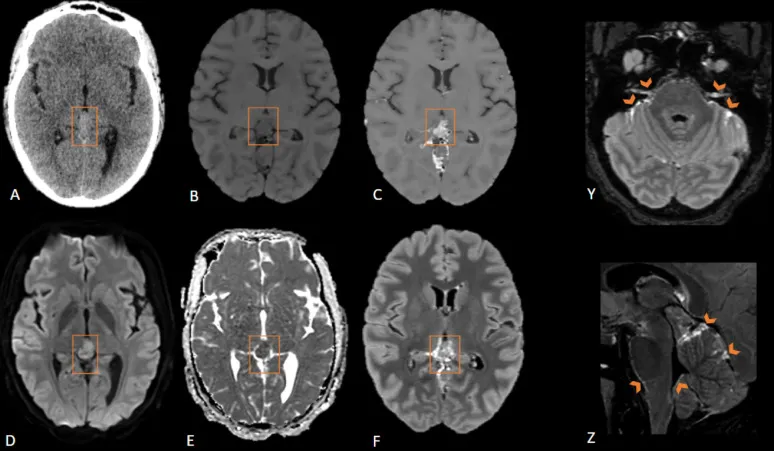

神经影像学综述《Neuroimaging in emergency: a review of possible role of pi...